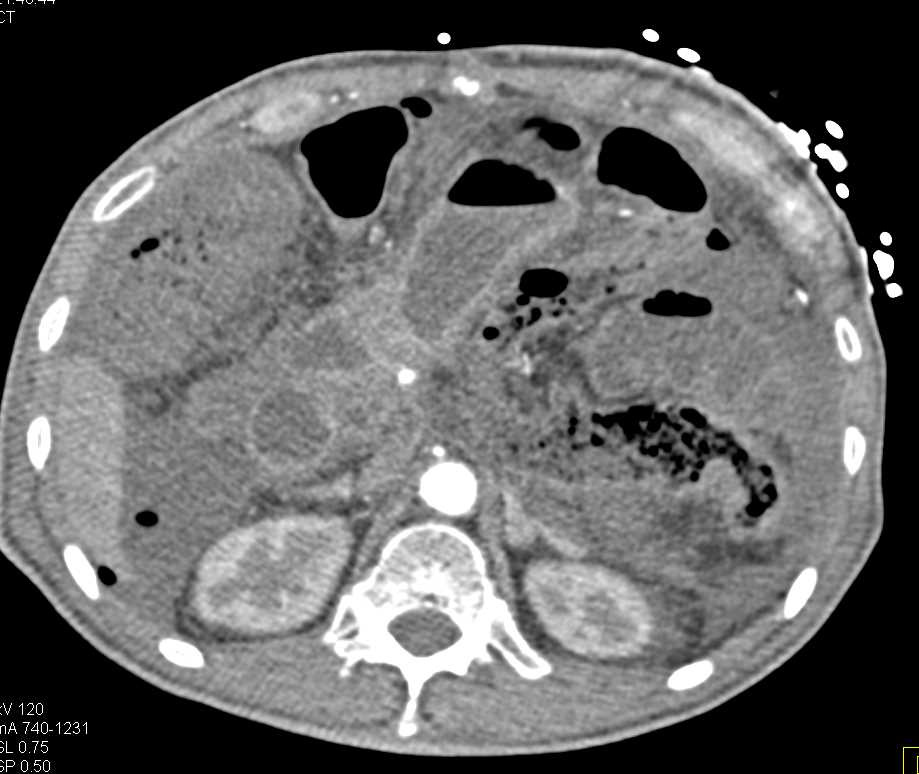

G-Tube Poorly Positioned Outside of the Stomach